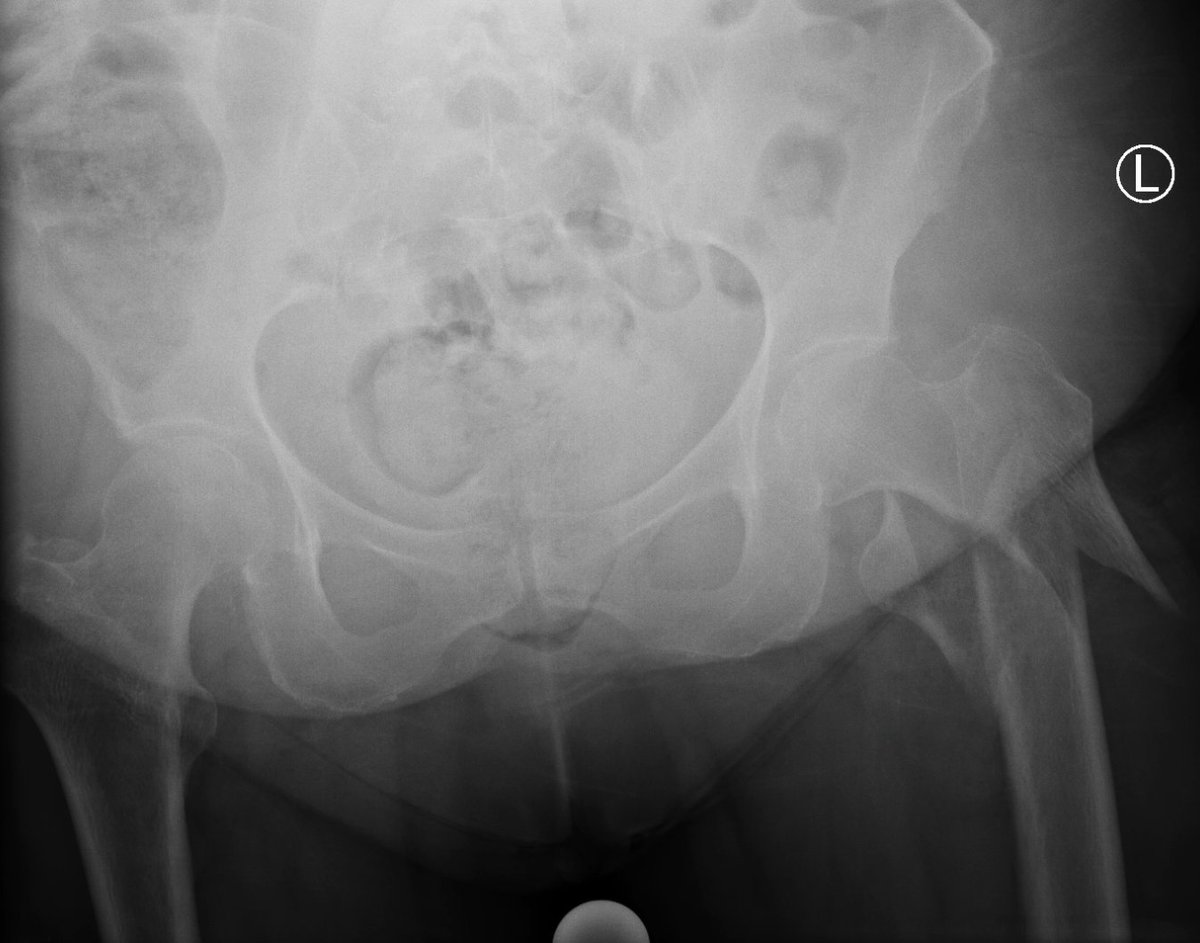

Percutaneous acetabular fixation

Dr. Diego López tweet mediaDr. Diego López tweet mediaDr. Diego López tweet media